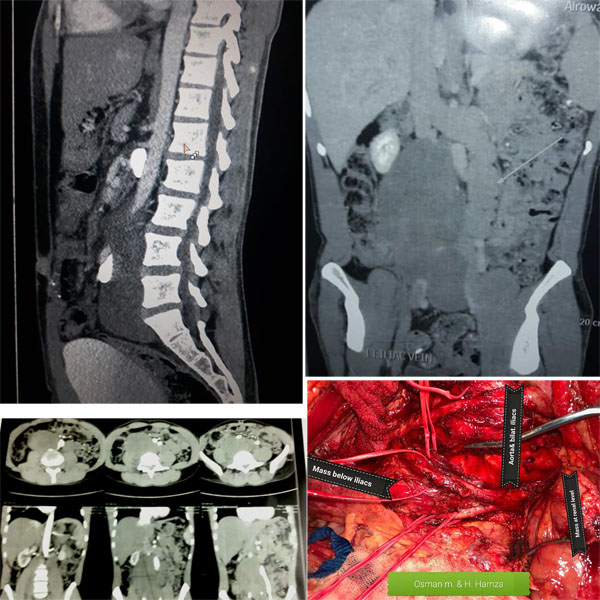

Historic Event In vascular surgery and oncology surgery in Egypt